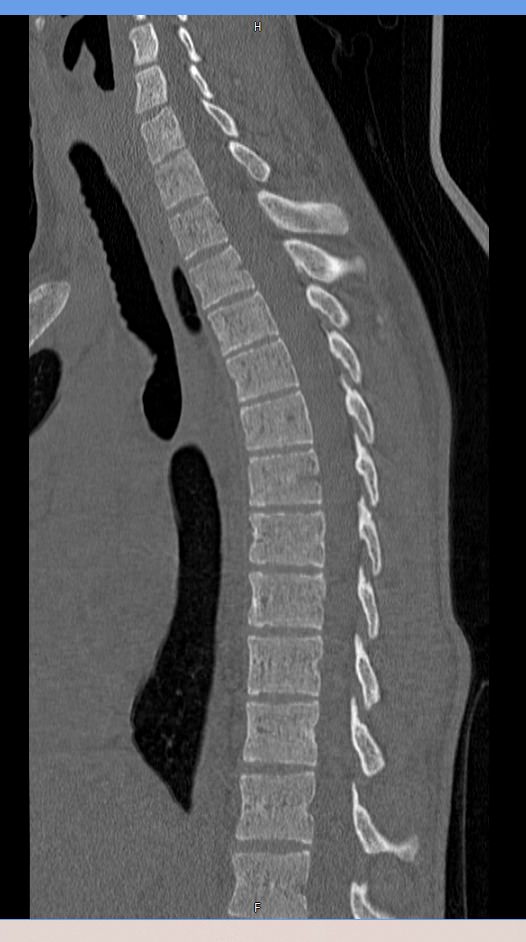

Мультиспиральная компьютерная томография – это современный быстрый и точный способ диагностики заболеваний позвоночника, основанный на использовании рентгеновского излучения. Метод позволяет получать послойные изображения грудного сегмента позвоночного столба, включая 12 грудных позвонков, задние отрезки ребер, межпозвоночные диски, позвоночный канал.

При помощи инновационных компьютерных программ данные преобразуются в трехмерные изображения позвоночного столба с сосудами, нервами и лимфатическими узлами в мельчайших подробностях. Наглядные объемные 3D-изображения высокого качества помогают в диагностике различных заболеваний позвоночника и бывают особенно полезны при планировании хирургических операций, при оценке эффективности проведенного лечения.

Что показывает компьютерная томография грудного отдела позвоночника

- изменения структуры и расположения позвонков и окружающего их мышечно-связочного аппарата

- аномалии развития позвоночника

- травмы позвоночного столба (переломы и трещины)

- ширину спинномозгового канала

- признаки наличия межпозвоночной грыжи (протрузии, экструзии)

- абсцессы, туберкулёзное поражение, новообразования, наличие метастазов и прорастание опухолей из соседних органов

- изменения в спинном мозге (кровоизлияния и др.)

- дегенеративные изменения

- участки пониженной плотности кости — остеопороз при визуальной оценке